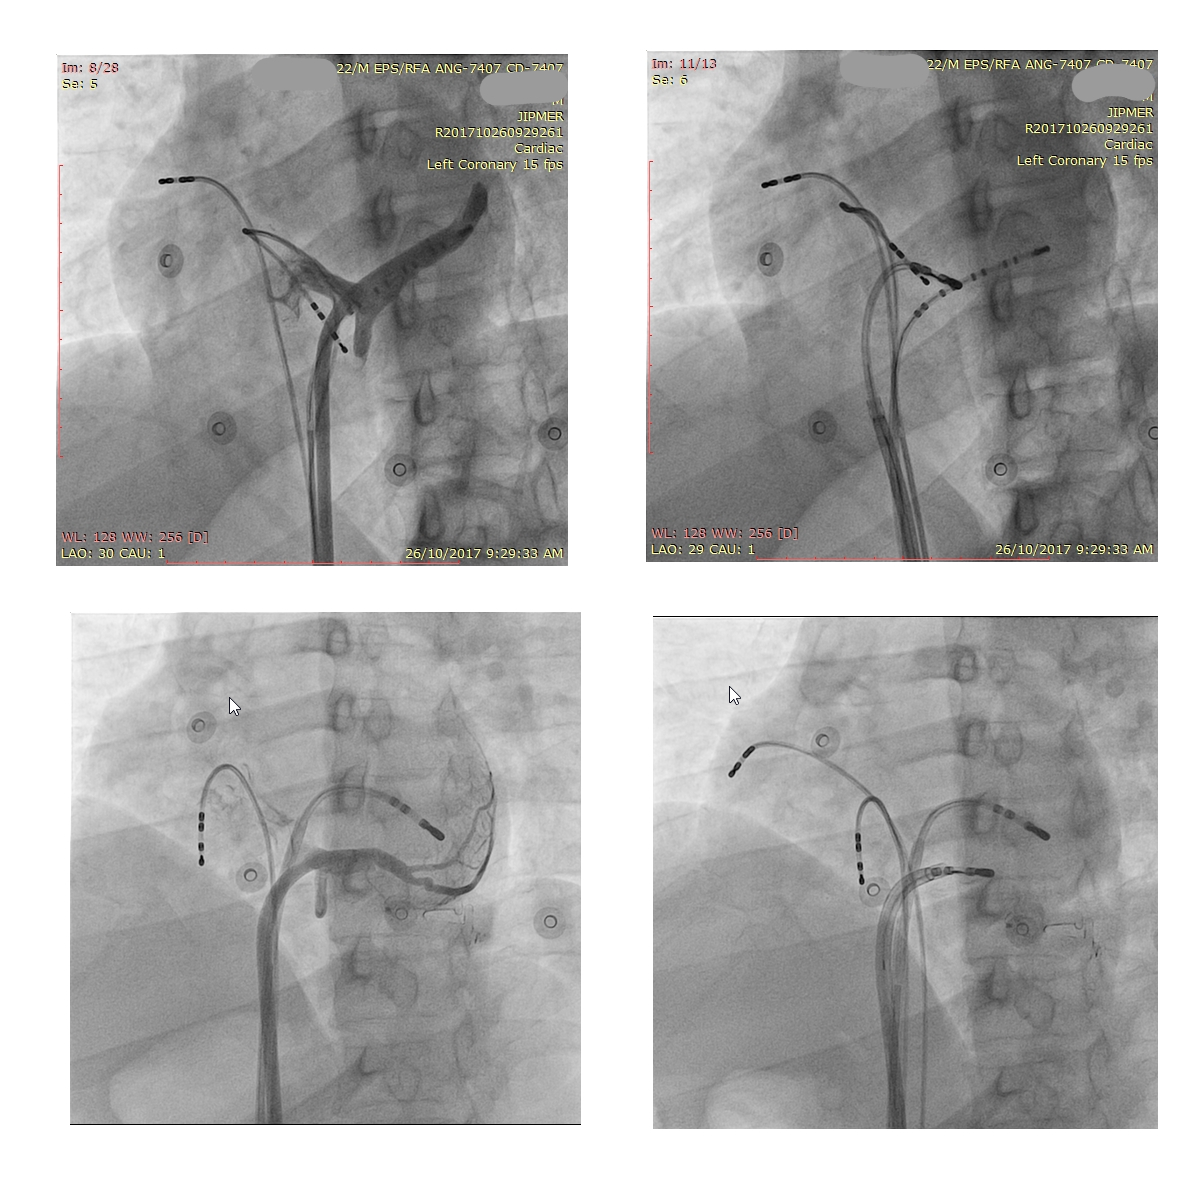

Mapping in diverticulum

diverticulum.jpg

med_lat_div.jpg

signals.jpg

Mapping in diverticulum - CSE potential most important

div_schematic.jpg

Selvaraj RJ et al. Radiofrequency ablation of posteroseptal accessory pathways associated with coronary sinus diverticula. J Interv Card Electrophysiol. 2016 Nov;47(2):253-259. doi: 10.1007/s10840-016-0113-x.